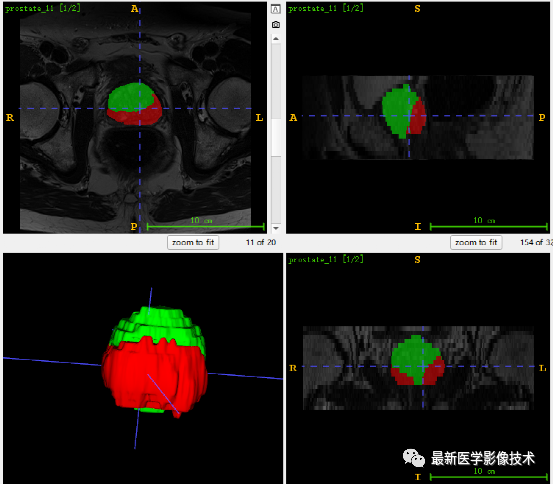

5、验证集分割结果

左边是金标准结果,右边是网络预测结果。